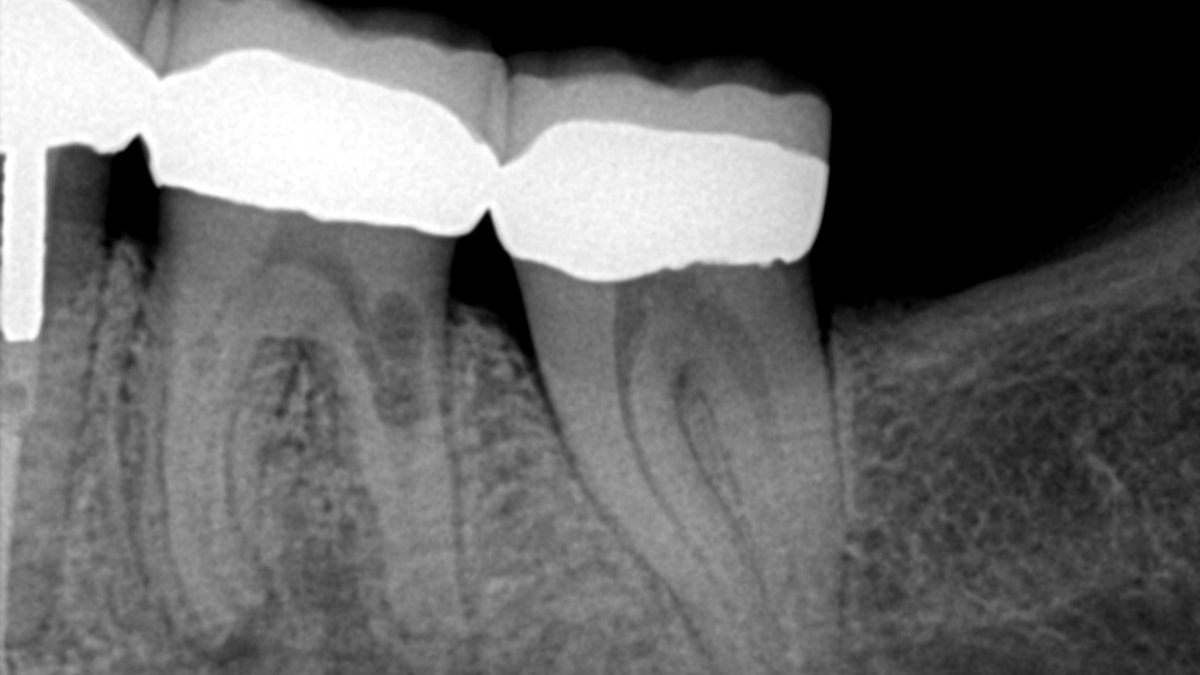

Dental Bone Resorption. Web root resorption has been defined as the loss of dental hard tissue as a result of osteoclastic cell action 1 and can. Web resorption is the term for a common type of dental injury or irritation that causes a loss of a part or parts of a tooth. Web tooth and root resorption involves parts of the tooth being broken down by cells called osteoclasts. Web explore what dental bone resorption and what role it plays in dental health. Web several factors, including tooth extraction, orthodontic complications, infection, and disease, can result in dental. According to the american association of. Web bone resorption is part of a complex biological process that can result in shrinkage or loss of bone. Can be caused by trauma to the tooth, such as a fracture or injury. Learn how to fix bone resorption. Here's how it may affect your mouth.

Here's how it may affect your mouth. Web bone resorption is part of a complex biological process that can result in shrinkage or loss of bone. Web tooth and root resorption involves parts of the tooth being broken down by cells called osteoclasts. Can be caused by trauma to the tooth, such as a fracture or injury. Learn how to fix bone resorption. Web several factors, including tooth extraction, orthodontic complications, infection, and disease, can result in dental. Web root resorption has been defined as the loss of dental hard tissue as a result of osteoclastic cell action 1 and can. Web explore what dental bone resorption and what role it plays in dental health. Web resorption is the term for a common type of dental injury or irritation that causes a loss of a part or parts of a tooth. According to the american association of.

Dental Bone Resorption Web several factors, including tooth extraction, orthodontic complications, infection, and disease, can result in dental. Here's how it may affect your mouth. Web several factors, including tooth extraction, orthodontic complications, infection, and disease, can result in dental. Web root resorption has been defined as the loss of dental hard tissue as a result of osteoclastic cell action 1 and can. Learn how to fix bone resorption. Web explore what dental bone resorption and what role it plays in dental health. Web resorption is the term for a common type of dental injury or irritation that causes a loss of a part or parts of a tooth. Can be caused by trauma to the tooth, such as a fracture or injury. Web tooth and root resorption involves parts of the tooth being broken down by cells called osteoclasts. According to the american association of. Web bone resorption is part of a complex biological process that can result in shrinkage or loss of bone.